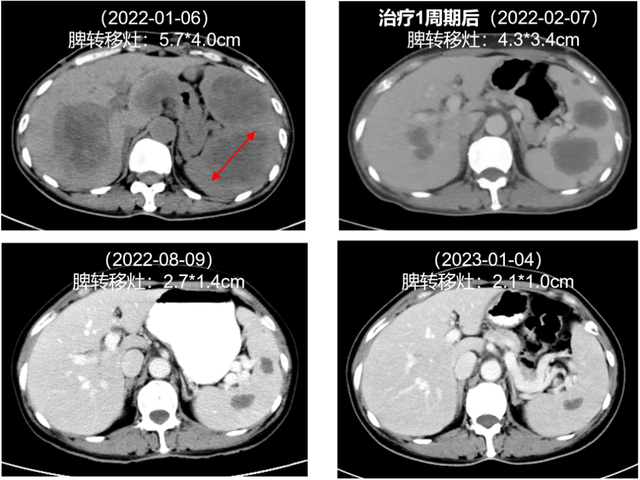

2022年1月7日,患者开始接受达拉非尼(150mg bid)+曲美替尼(2mg qd)一线治疗,联合双磷酸盐抗骨代谢治疗。治疗1周期(2022年2月7日)后,肝转移灶、脾转移灶和皮下转移灶缩小,肾盂转移灶消失。最新复查结果(2023年1月4日)显示,肝转移灶、脾转移灶稳定控制,病情持续控制中。

图3. 治疗前后脾转移灶变化